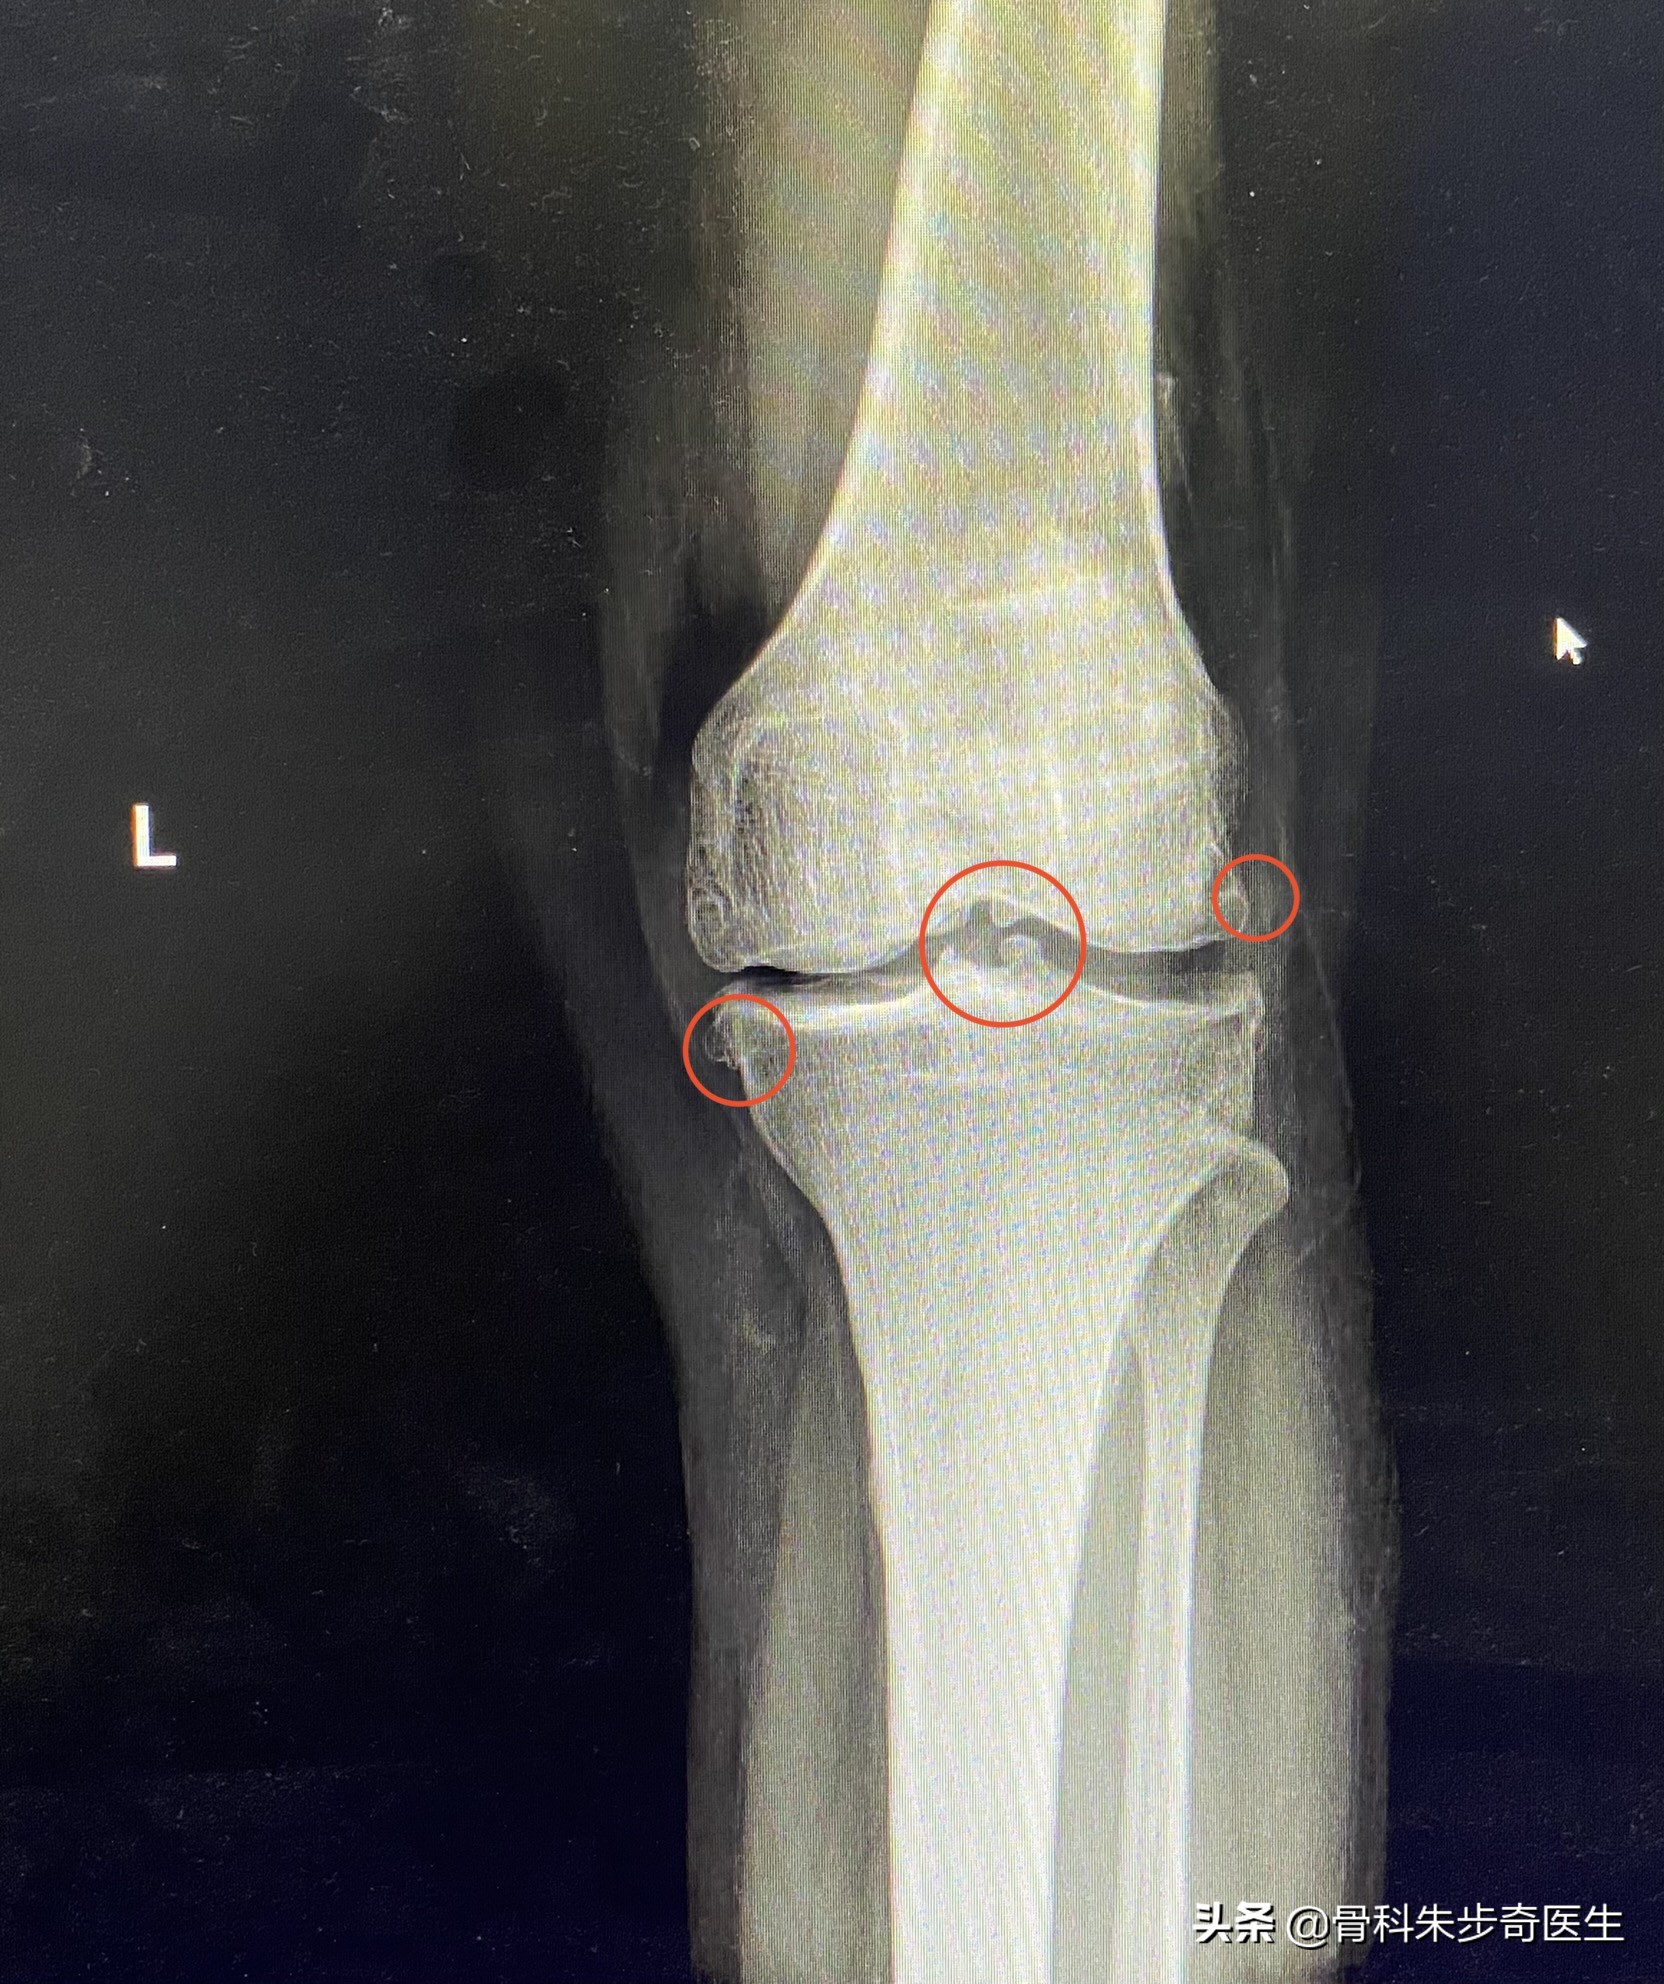

先不看片子,先检查一下膝关节:首先能够发现,膝关节有点肿胀,查了一下,髌骨上方的关节囊确实有积液,同时,髌骨下方的关节面也有退变,半月板也有问题,于是看了下片子:

从片子上可以看出来,这些红色标记的地方都是骨质增生,也就是我们说的骨刺,但是骨刺本身并不是什么问题,我曾经反复强调过,骨刺本省不会引起任何症状,引起症状的是内部的软骨退变,游离体,半月板损伤,这些才是因,骨刺最后只是结果而已。

但是因为她的膝关节肿胀,关节内部还有游离体,说明内部关节退变比较严重,这个时候给她解释道,您这个关节不只只是骨刺的问题,更多的是关节内部的软骨有退变了,而且还有游离体,这个游离体得取出来,不取的话会把关节搞坏了,所以还是建议住院做个小手术,把游离体取出来,顺便清理一下关节。